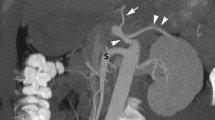

Case 2: anterior (a) and lateral (b) selective 3D volume rendering views of the gastrointestinal arteries. The celiac trunk (black arrow) and the superior mesenteric artery (short black arrow) appear of relatively small caliber and their emergences from the aorta are extremely constricted at the level of the arcuate ligament of the diaphragm (white arrowhead). The gastroduodenal artery also has a rather small caliber (white star). A long and large tortuous anastomosis from a large inferior mesenteric artery provides general substitution (white arrows). A small aneurysm is visible on the anastomosis of the gastroduodenal artery and the superior mesentery artery (in the white circle). Anterior (c) and lateral (d) selective 3D volume rendering views of the hepatic artery (black star) show the course of a long and tortuous anastomosis between the falciform (small black arrows) artery and the superior epigastric artery (long white arrows)

Case 2: a series of three axial MIP views obtained at the level of the falciform ligament (a–c) and another series of coronal MIP views at the same level (d–f) clearly illustrate the long tortuous anastomosis between the falciform (small white arrows) artery and the superior epigastric artery (small black arrow). The long and large tortuous anastomosis from the large inferior mesenteric artery (white arrows), the gastroduodenal artery (star) and the small caliber superior mesenteric artery (grey arrow) are also visible